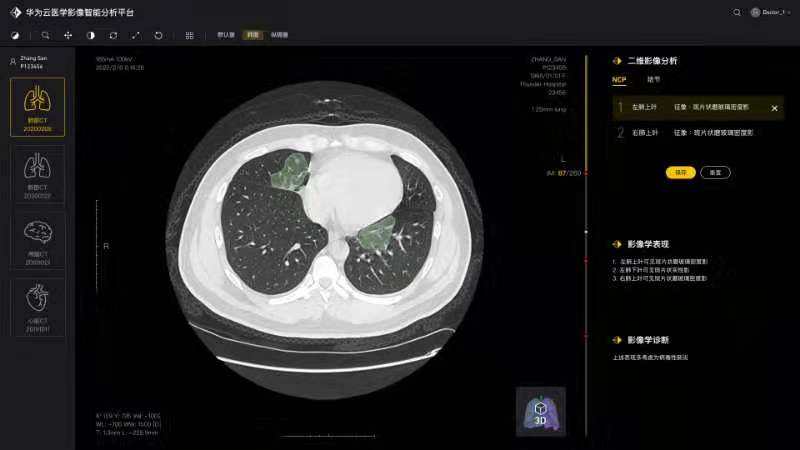

将论文写在祖国的大地上,加快加强疫情防控科研攻关,服务一线疫情防控救治——疫情发生以来,由学院白翔、许永超等老师负责的华中科技大学—华为智能创新实验室积极发挥自身优势,组织团队师生争分夺秒抓紧开展高质量科研攻关,与附属协和医院放射科、华为云、篮网科技等团队共同研发出一套基于人工智能技术的面向新冠肺炎肺部CT影像量化分析系统。2月29日下午,中共中央政治局委员、国务院副总理孙春兰率中央指导组来校考察疫情防控科研攻关情况,许永超副教授当场向孙副总理介绍了研发推出该系统的工作及成果。该系统可以辅助医生更高效地区分新冠肺炎的早期、进展期与重症期,有利于早期筛查与防控。同时,对于确诊病人,基于对多次复查影像数据的量化分析,医生能够有效评估病情进展及用药疗效等情况。目前该系统已在全国几十家医院使用,日均调用量3000多次。孙春兰肯定了研究团队所开发系统的精确性,可以辅助医生定量分析,大幅提升效率,缓解影像医生的压力。她非常关注该系统的落地应用情况,特别是在湖北省、武汉市的应用,鼓励团队结合CT影像与核酸试剂等信息,进行更为精准的新冠肺炎诊断。